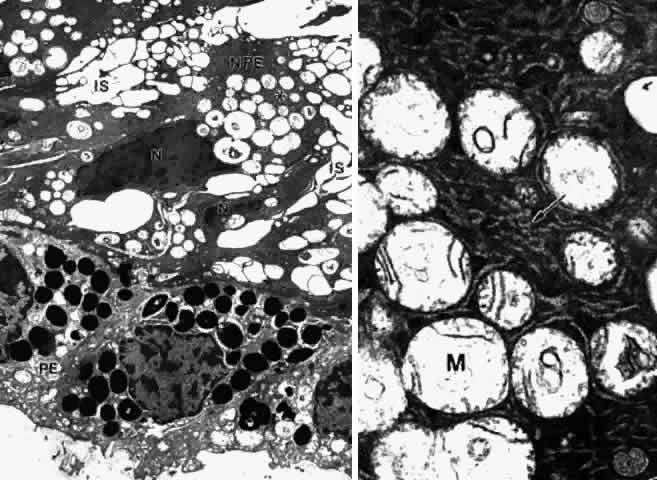

processes.  Fig. 18. Posterior pars plana. A. Nonpigmented epithelial (NPE) cells appear tilted

and compressed with dense cytoplasm. The extensive cystic dilatation

of the intercellular spaces (IS) around these cells is characteristic

of this region. Only the nucleus (N) and the many hydropic mitochondria

are visible in the cytoplasm. The basement membrane under the pigment

epithelium (PE) is multilaminarand thick. (X 5700) B. Higher magnification

of asterisked region in A shows that the cytoplasm is full of

branching and curved profiles of smooth endoplasmic reticulum (arrow), which

is also typical of this region. M, mitochondrion. (X 22,000) Fig. 18. Posterior pars plana. A. Nonpigmented epithelial (NPE) cells appear tilted

and compressed with dense cytoplasm. The extensive cystic dilatation

of the intercellular spaces (IS) around these cells is characteristic

of this region. Only the nucleus (N) and the many hydropic mitochondria

are visible in the cytoplasm. The basement membrane under the pigment

epithelium (PE) is multilaminarand thick. (X 5700) B. Higher magnification

of asterisked region in A shows that the cytoplasm is full of

branching and curved profiles of smooth endoplasmic reticulum (arrow), which

is also typical of this region. M, mitochondrion. (X 22,000)